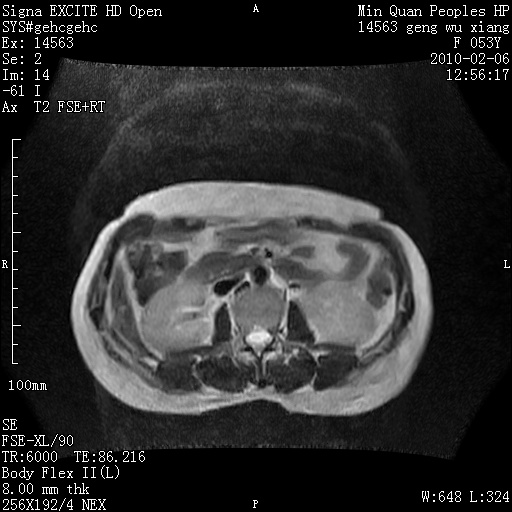

标题: MRI2762:胆道梗阻原因?

f,53y,全身黄染多日。

高位胆道梗阻 胆管癌可能性大

支持 高位胆道梗阻 胆管癌可能性大。